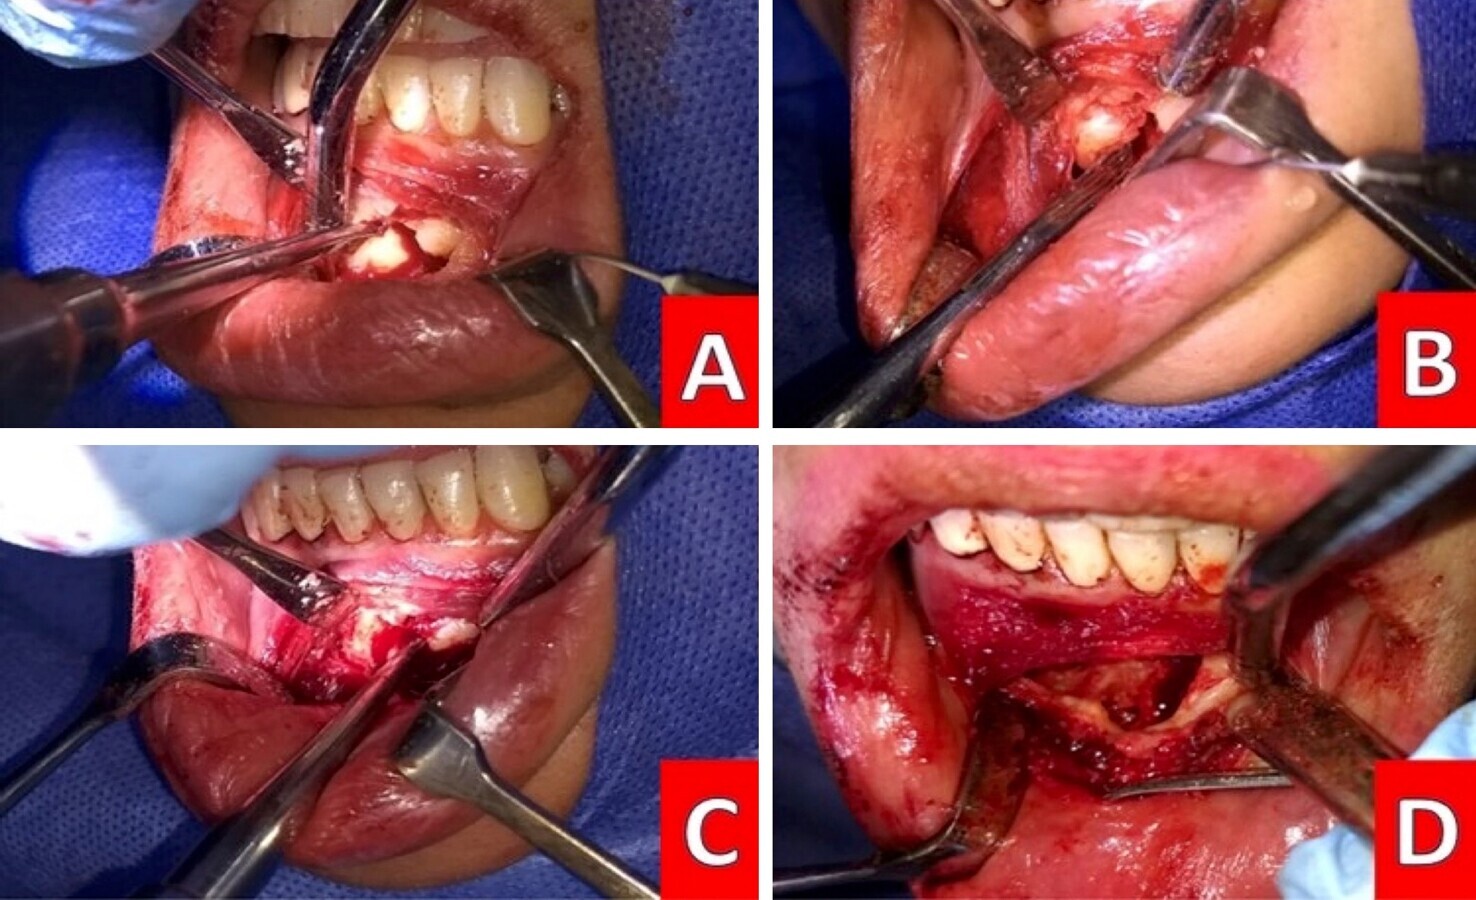

Figura 3. A) Anestesia e incisión para colgajo de espesor total en alas de gaviota. B) Despegamiento y enucleación del granuloma. C) Curetaje del nicho remanente. D) Remodelación de ápice.

Con el colgajo definido, se localizó la zona de la lesión y el ápice; cuidando no involucrar el espacio radicular adyacente de las piezas 21 y 23, se enucleo y extirpó la cápsula de la lesión mediante curetaje con posterior legrado en el nicho remanente (Figura 3). Tras este paso, se remodelo el ápice, a baja velocidad con fresa de fisura 701 de carburo y a continuación se realizó el tratamiento inmediato del conducto, finalizando la obturación con técnica de clororopercha y plastificado. Terminado este paso, se irrigo el nicho con agua fría estéril (Figura 4).